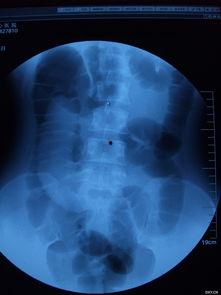

四、成人肠套叠的诊断

成人肠套叠的诊断主要依靠以下方法:

1. 影像学检查:如X光、CT、MRI等,可以清晰地显示肠套叠的情况。